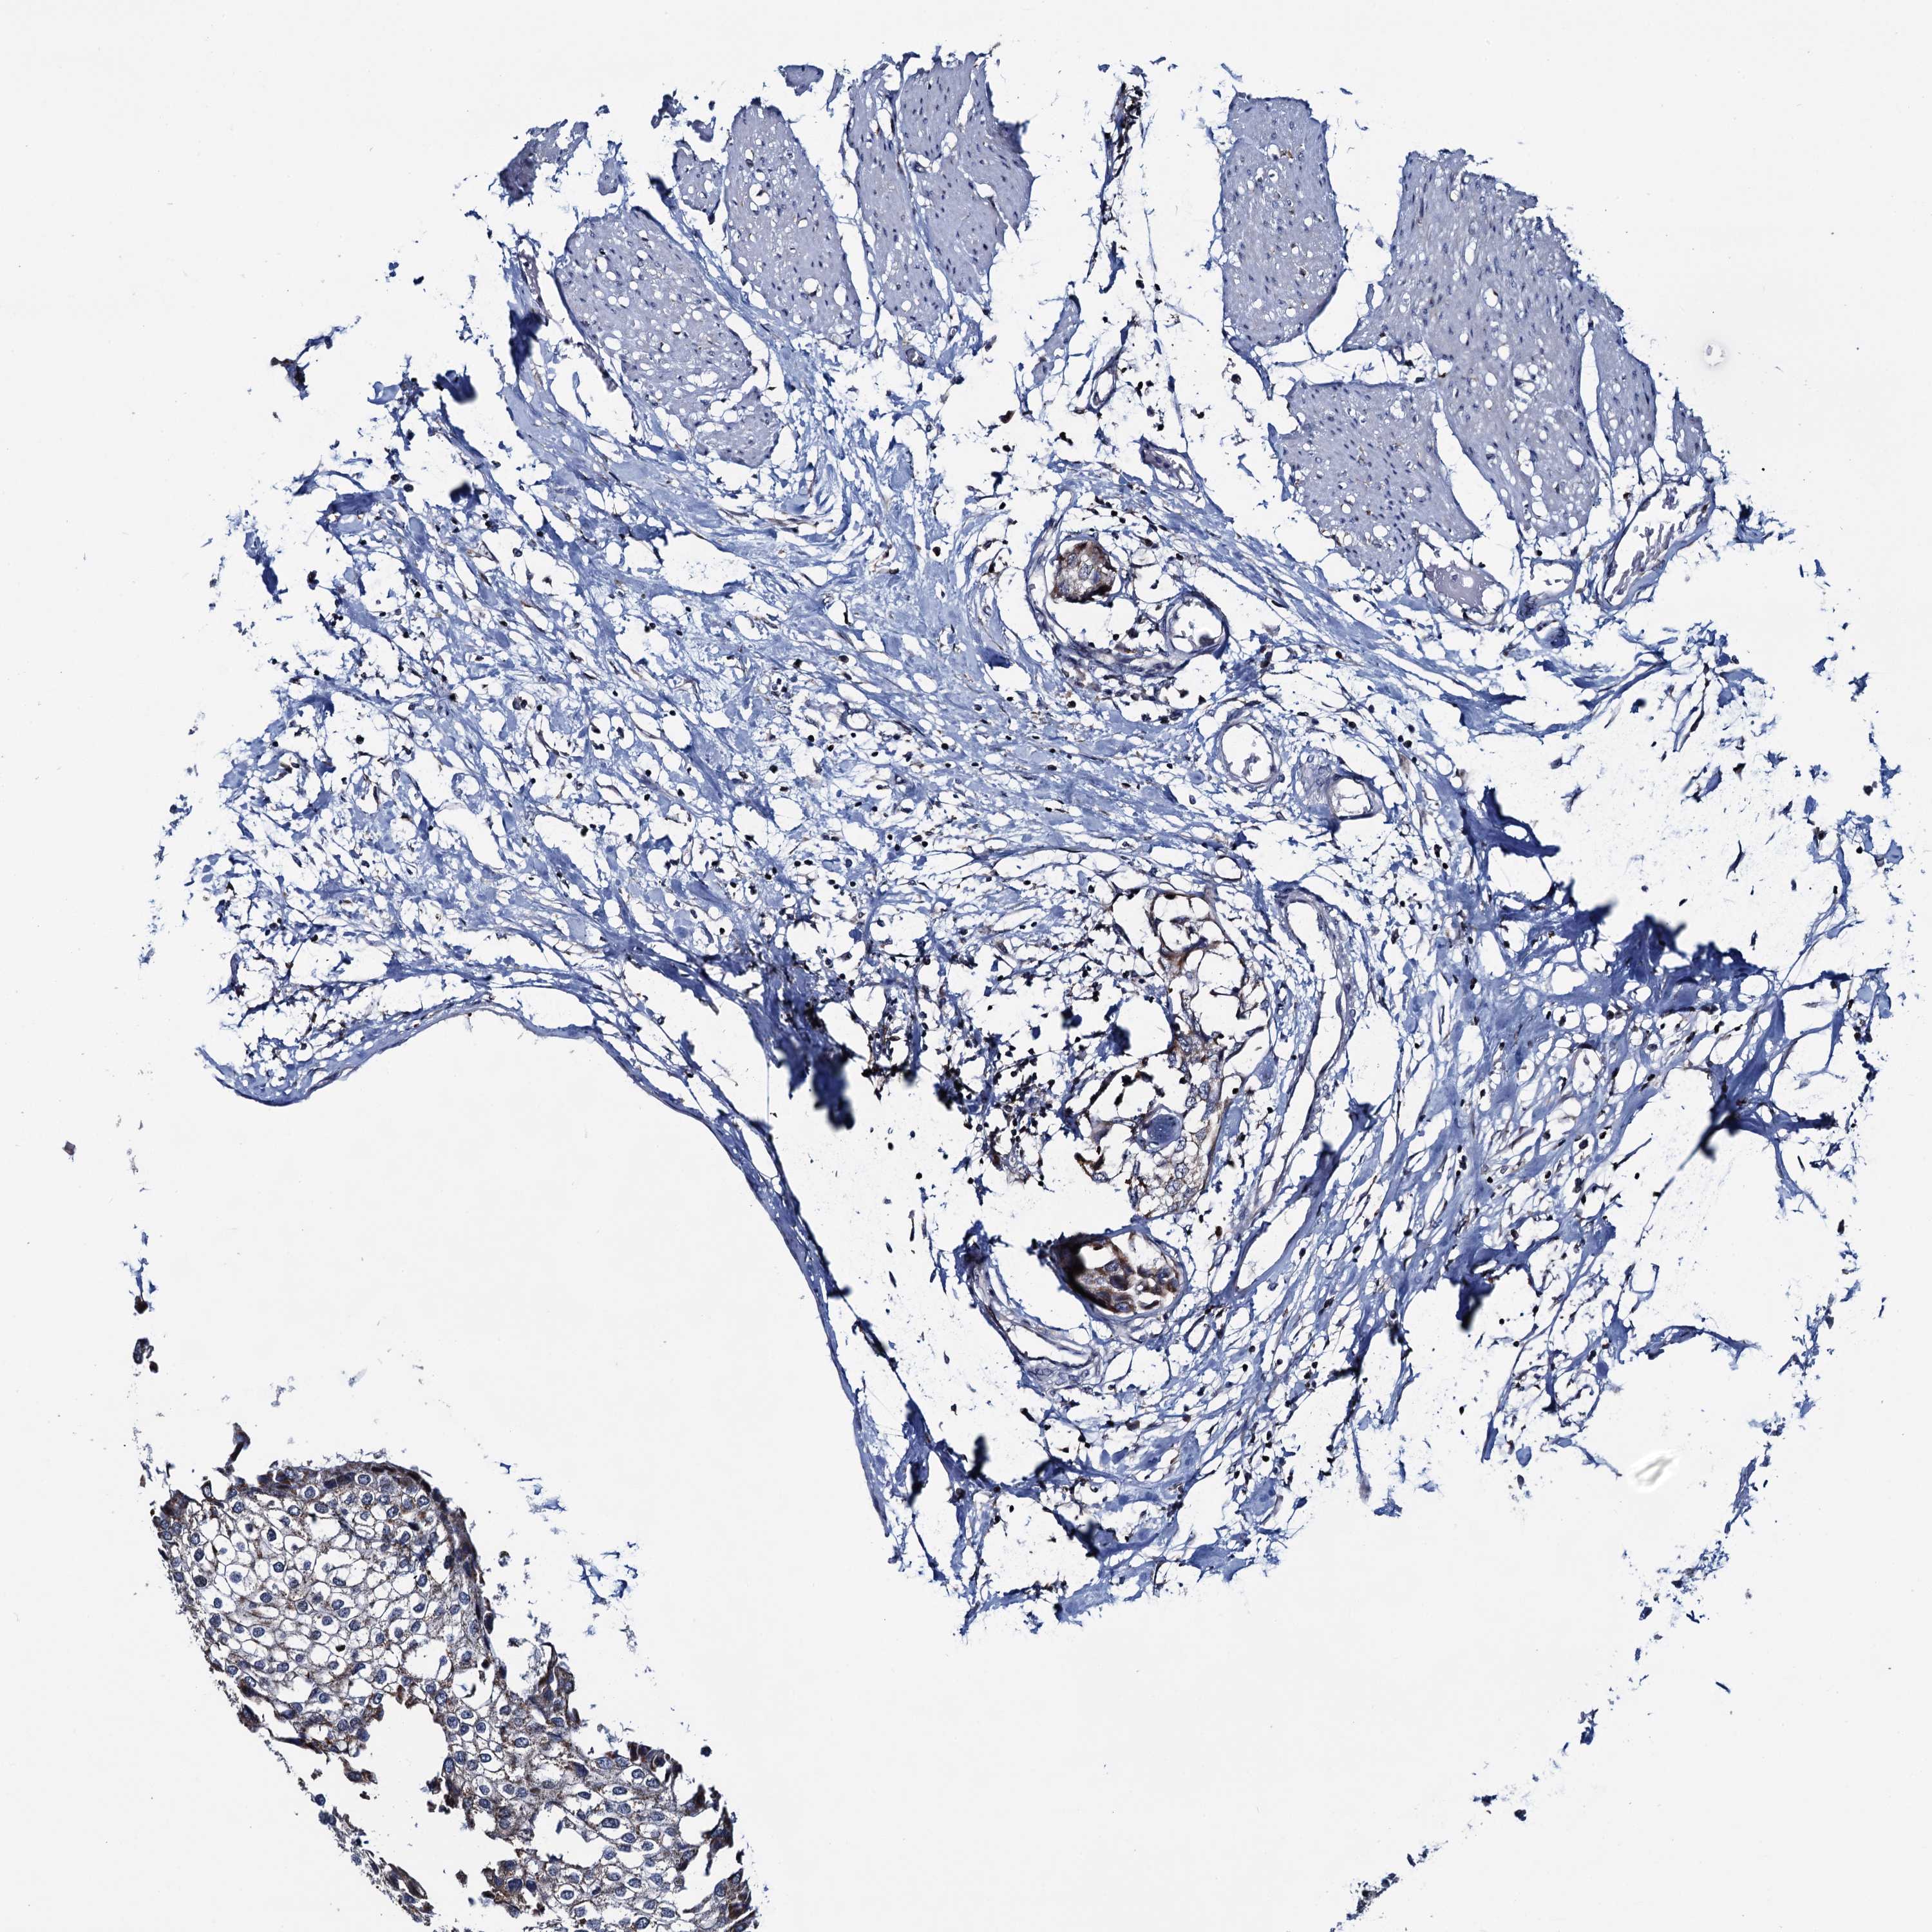

UROTHELIAL CANCER - Protein expressioni

A mouse-over function shows sample information and annotation data. Click on an image to view it in a full screen mode. Samples can be filtered based on level of antibody staining by selecting one or several of the following categories: high, medium, low and not detected. The assay and annotation is described here.

Antibody stainingi

Antibody staining in the annotated cell types in the current human tissue is reported as not detected, low, medium, or high, based on conventional immunohistochemistry profiling in selected tissues. This score is based on the combination of the staining intensity and fraction of stained cells.

Each image is clickable and will lead to virtual microscopy that enables deeper exploration of all samples and also displays staining intensity scores, fraction scores and subcellular localization as well as patient and tissue information for each sample.

Antibody HPA040598

Antibody HPA040958

Urothelial carcinoma, High grade